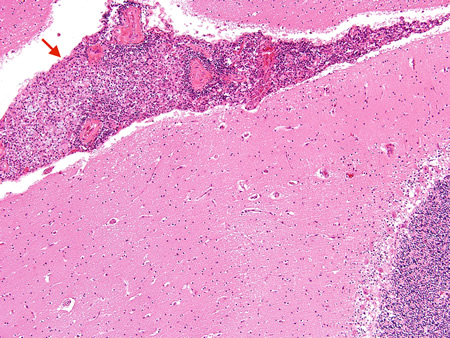

Biópsia do cérebro de paciente imunocompetente com meningite criptocócica sob baixa magnificação exibindo meninges com inflamação (seta vermelha)

Do acervo pessoal de Robert E. Schmidt; usado com permissão